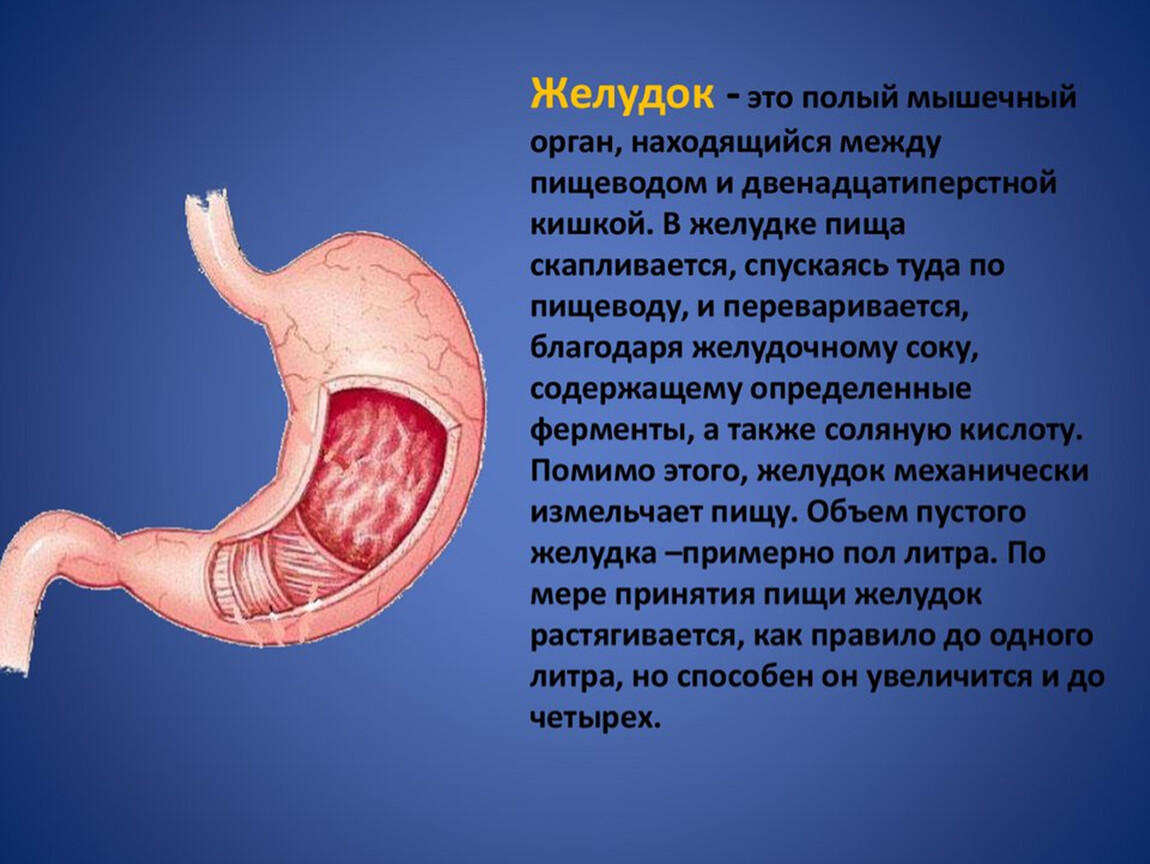

Анатомия желудка и сердца: визуализация и изучение